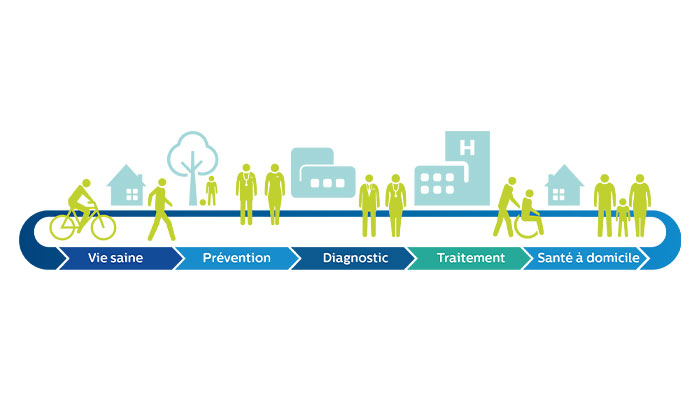

Philips s'engage pour un monde plus sain et plus durable en concevant des solutions qui ont un impact positif pour les patients et l'environnement. Nous savons que c'est important pour vous aussi. C'est pourquoi nous avons développé un éco-passeport qui explique la performance environnementale de nos produits et vous permettre de choisir en toute transparence.

Des solutions pour un workflow optimisé

Optimisation du workflow

Avec SmartWorkflow, atteignez une productivité élevée tout en permettant à votre personnel de se concentrer sur les patients.

Philips Radiology Workflow Suite

Des solutions d'optimisation pour l'ensemble du parcours d'imagerie (préparation, acquisition, interprétation et partage des résultats et suivi patient).